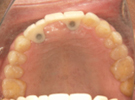

50代女性

![]() |

治療前 |

||

治療中。仮歯。 左上の奥にインプラント埋入。 噛みあわせ治療を行いました |

治療後 全体の歯で食事がおいしくできるようになったと喜んでおられました。 |